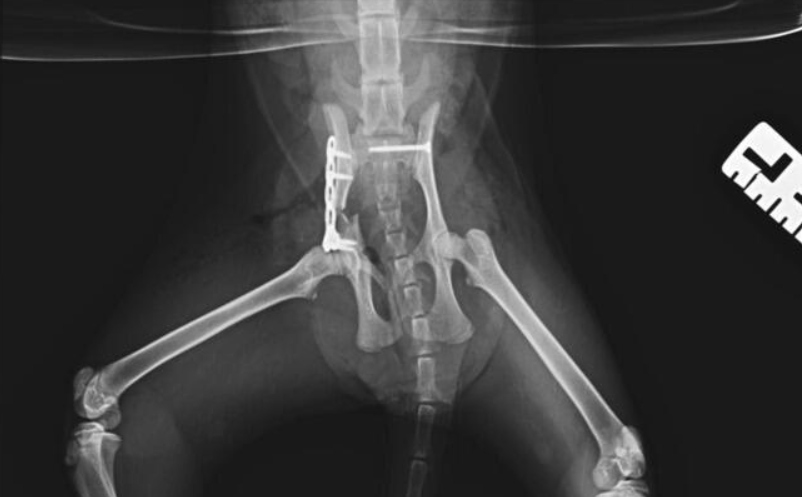

Kotka została znaleziona pod blokiem przez cudowną osobę, która nie pozostała obojętna i natychmiast powiadomiła odpowiednie służby! W wyniku upadku Felcia odniosła bardzo poważne obrażenia: przesunięcie kręgów w odcinku krzyżowym kręgosłupa, złamanie miednicy i zwichnięcie stawu biodrowego. Na szczęście zachowała czucie, więc mamy wielką nadzieję na powrót małej do pełnej sprawności, do czego długa droga...

Kicia jest już pod opieką naszej fundacji! Jest już po skomplikowanej operacji, której podjął się znakomity ortopeda, doktor Kacper Weigel. Z całego serca dziękujemy Panu doktorowi oraz całemu zespołowi Kliniki Weterynaryjnej Puławska za błyskawiczną pomoc i zaangażowanie! Wszystko się udało i po 6 tygodniowym unieruchomieniu w kennelu rozpoczniemy rehabilitację.